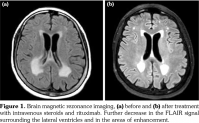

Autoimmunity and the overall state of chronic inflammation are associated with many extra- articular manifestations.(1) Rheumatoid vasculitis is probably the rarest yet the most severe extraarticular manifestation and is usually observed in patients with long-standing, uncontrolled seropositive disease.(2) In this article, we describe the case of a 61-year-old female patient diagnosed with seropositive long-standing rheumatoid arthritis presented to our hospital recently and episodic fluctuations of altered level of consciousness of one week duration, initially diagnosed to have bacterial meningitis based on cerebrospinal fluid analysis with superimposed pneumonia and started on antibiotics with no improvement. Patient is known to have multiple rheumatoid nodules in her chest, followed-up by serial computed tomography scans. Magnetic resonance imaging (MRI) of the brain upon admission showed multiple confluent high fluid- attenuated inversion recovery (FLAIR) signals in the periventricular white matter, hippocampal gyrus and peritrigonal regions of both cerebral hemispheres (Figure 1). In light of the patient’s known diagnosis of rheumatoid arthritis, these findings were compatible with an inflammatory process consistent with rheumatoid vasculitis. Repeated cerebrospinal fluid analysis after antibiotics treatment indicated increased number of inflammatory cells, mainly lymphocytes and monocytes. Open lung biopsy revealed active chronic interstitial pneumonitis (Figure 2). It was then decided to start our patient on steroids: intravenous methylprednisolone 40 mg push twice daily and antibiotics were discontinued with the diagnosis of rheumatoid cerebral vasculitis. She was then discharged on prednisone 40 mg orally once daily.

Repeated MRI of the brain one month later displayed significant decrease in the high FLAIR signals. Repeated lumbar puncture and cerebrospinal fluid analysis three months later demonstrated mature lymphocytes and occasional monocytes. Decision was to proceed with rituximab infusions as a steroid-sparing agent. Repeated MRI and cerebrospinal fluid studies three months after first cycle of rituximab showed significant improvement. Cerebral vasculitis is a rare complication of rheumatoid arthritis with frequency ranging between 1% and 8%.(3) The damage in the endothelium may trigger thrombus formation which might result in ischemia or hemorrhage in the area served by the vessel that can be seen on the macroscopic level.(4) Rheumatoid vasculitis is most commonly seen in seropositive females with destructive and erosive rheumatoid arthritis associated with subcutaneous nodules and other extraarticular manifestation.(4) A biopsy is required for a definitive diagnosis of cerebral vasculitis. However, it is not always feasible and mostly based on cerebrospinal fluid and cerebral imaging studies. Cerebrospinal fluid would demonstrate lymphocytosis and protein elevation which implies an underlying inflammation. There are no clear guidelines when it comes to treatment of cerebral vasculitis in rheumatoid arthritis. However, glucocorticoids have been commonly used such as pulse methylprednisolone.(5) In a study carried out by Puéchal et al.,(6) complete remission of cerebral rheumatoid vasculitis was observed in 12 out of 17 patients receiving rituximab. Our patient had significant response on intravenous methylprednisolone and rituximab that was shown by repeated MRI of the brain.